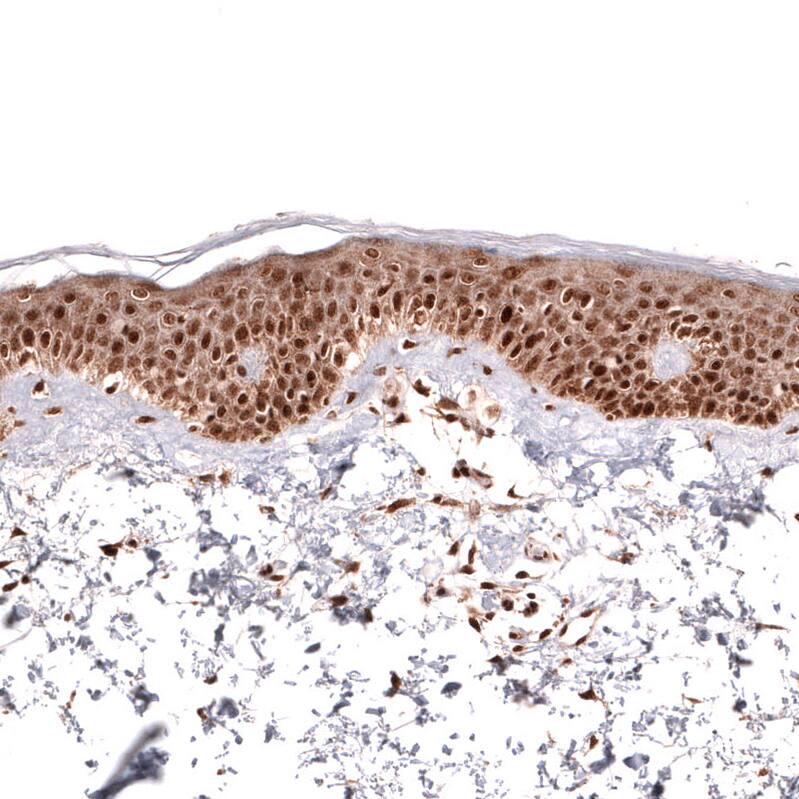

Immunohistochemistry-Paraffin: IL-33 Antibody (CL13438) [NBP3-24558]

Staining of human skeletal muscle shows no positivity in myocytes as expected.